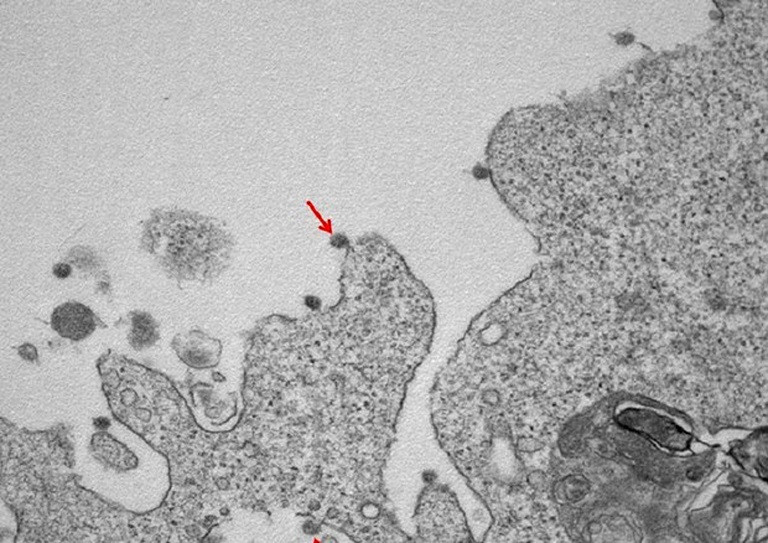

Oamenii de știință din Arabia Saudită au dat publicității cele mai noi imagini ale coronavirusului, de această dată putând fi observată atât structura externă a acestuia, cât și cea internă.

Vezi în Galeria Foto cum arăta noul coronavirus în urmă cu câteva luni